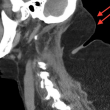

In particolare la paziente aveva dei rigonfiamenti sul collo e sulle braccia, oltre alla gobba pronunciata sulla schiena. Ai medici ha raccontato di aver iniziato a notare quelle protuberanze cinque anni prima, ma di non essersene preoccupata molto perché non le facevano male e non le interessava l’effetto estetico.

La deformità di Madelung, infatti, colpisce soprattutto le persone alcolizzate, anche se per lo più uomini piuttosto che donne. Questa patologia provoca dei tumori benigni chiamati lipomi che si formano soprattutto sulla schiena.

“Ad una prima osservazione abbiamo notato diversi rigonfiamenti su tutto il corpo, attorno al collo, sulla parte superiore della schiena e delle braccia”.